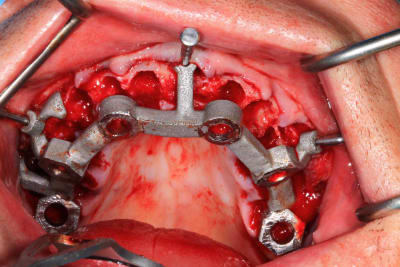

Le cas N°2 en images reelles :)

Guide métal avec support clavette, os assez fin : il est prévu un sticky bone complet : donc : lambeau avant extraction, positionnement du guide base et forage des clavettes, positionnement du guide implant, pose des piliers MU, controle des axes prothétique avec le guide pilier, collage des piliers prov sur le bridge a armature métal, occlusion nickel, sticky bone et PRF, sutures suspendues.

Et c’est confirmé par ton guide pour les piliers multiunits qui n’est même pas à fond (clavette antérieur pas mise….enfin certainement impossible à mettre)

Pour le guide pilier , c’était pile, mais je n’avais pas fais la photo. Je l’ai remis vite fais ( et mal ) pour la photo.

Le guide pilier est la réplique du bridge prov , en plus light pour une meilleure visibilité, donc, si je n’avais pas pu bien mettre le guide pilier, cela aurait été pire avec le bridge prov.

Mais tu peux me faire confiance.Le bridge prov était nickel, avec la clavette en place, sans que je ne doive meuler les puits préparés.

J’était vraiment content de n’avoir quasi aucune retouche d’occlusion.